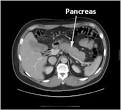

Sieht man ein diffus vergrößertes Pankreas, kann eine Autoimmun-Pankreatitis dahinter stecken. Die autoimmune Pankreatitis (AIP) Typ befällt Männer doppelt so häufig wie. Die wichtigste Differentialdiagnose zum Pankreaskarzinom stellt die Autoimmun. Pankreatitis Eine akute Pankreatitis zeigt sich durch heftigen Schmerz im Oberbauch.

Die autoimmune Pankreatitis (AIP) ist ein seltenes, jedoch komplexes Krankheitsbild.